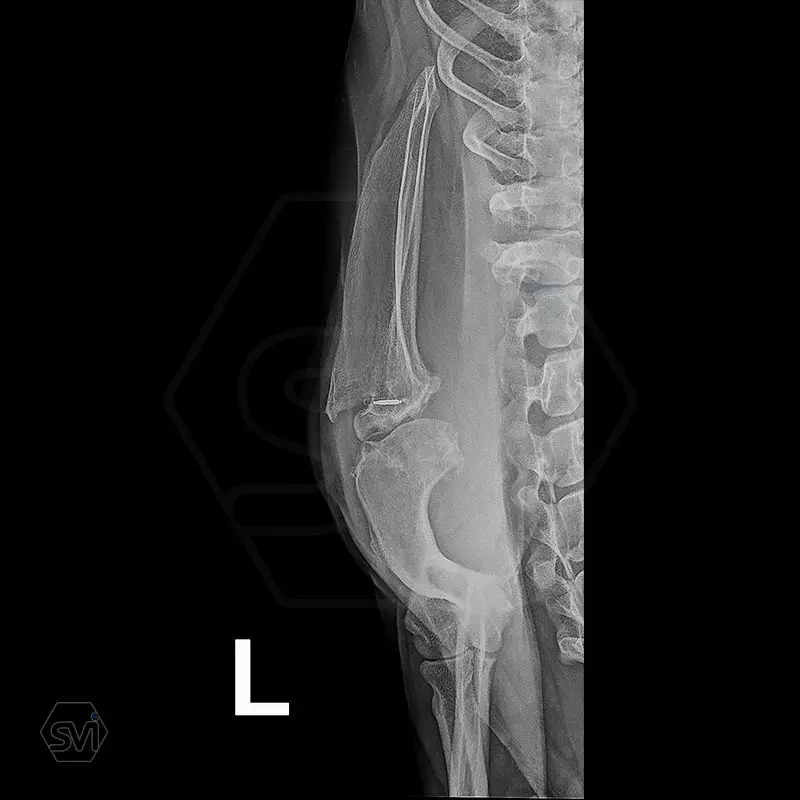

In our case, we created a shoulder arthrodesis on an 11-year-old 16kg female beagle dog with a 2.7 SOP-LC system and 4-4 clamps. The dog developed chronic arthritis and arthrosis, the biopsy did not confirm a tumor, only chronic inflammation.